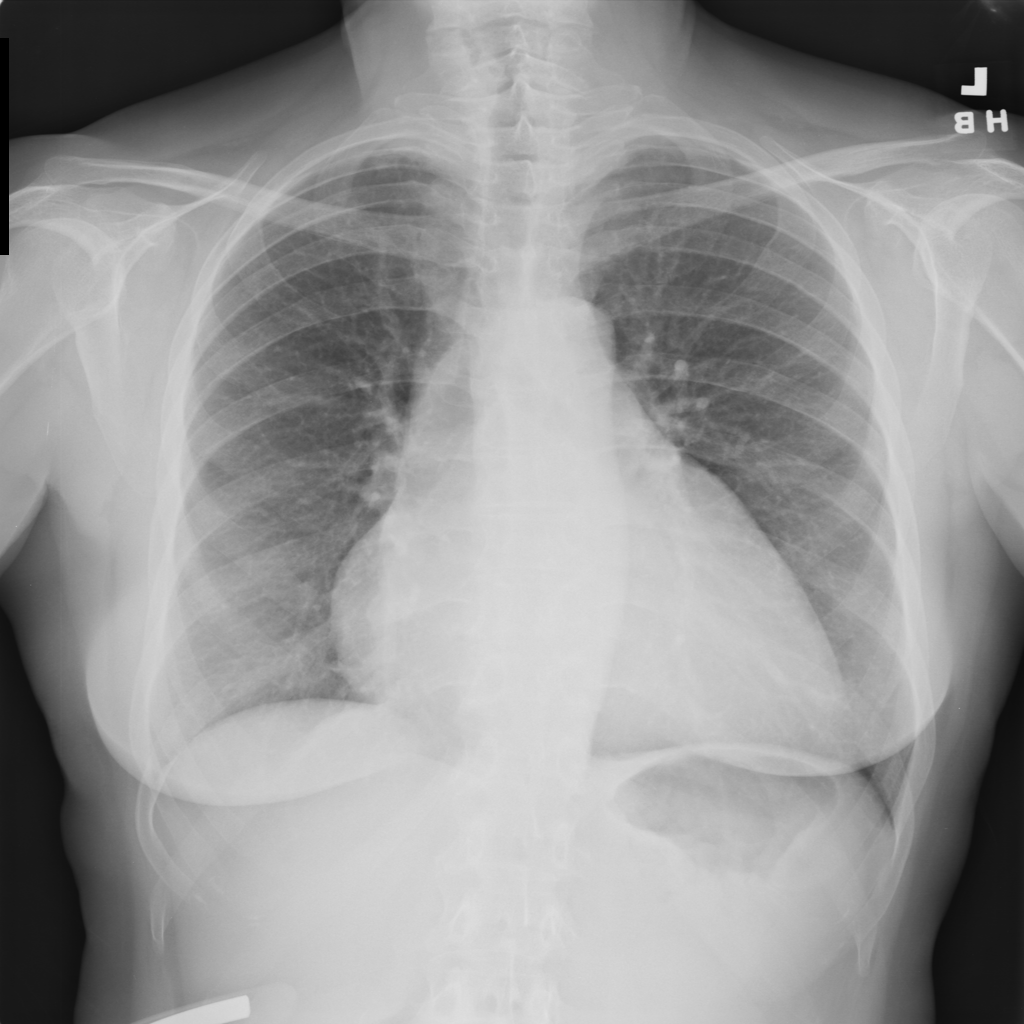

PAT-F3E7 · IMG-000Cardiomegaly

PAT-F3E7 · IMG-000

PA